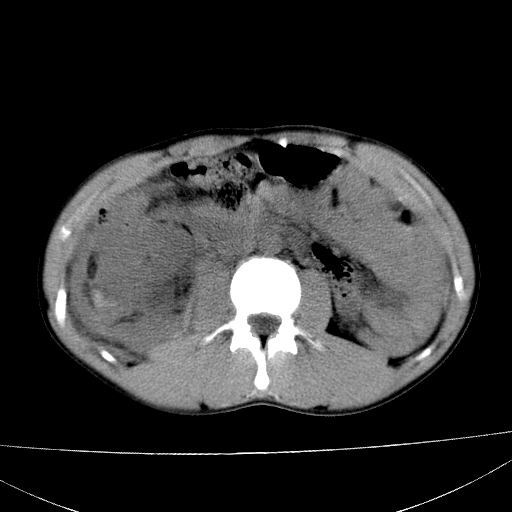

标题: CT15860:男,21岁,腹部外伤2小时伴胸疼。 [打印本页]

标题: CT15860:男,21岁,腹部外伤2小时伴胸疼。

肝脏及肾脏明显有损伤性改变并激发腹腔内积液(血),以肝脏撕裂及肾周积血显著。

1)肝破裂伴腹腔积液(血)。2)右肾破裂伴右肾包膜下及肾周血肿。3)腹部空腔脏器穿孔可能。4)右侧少量胸腔积液(血)。

肝肾挫裂伤,右肾周及包膜下血肿,腹腔积液,不排除空腔脏器穿孔,建议行增强检查

1肝挫伤伴腹腔积液。2右肾挫裂伤伴右肾包膜及肾后间隙肿血肿。3右肾脏周围的积气,十二指肠显示结构不清,考虑十二指肠降部破裂可能性大。